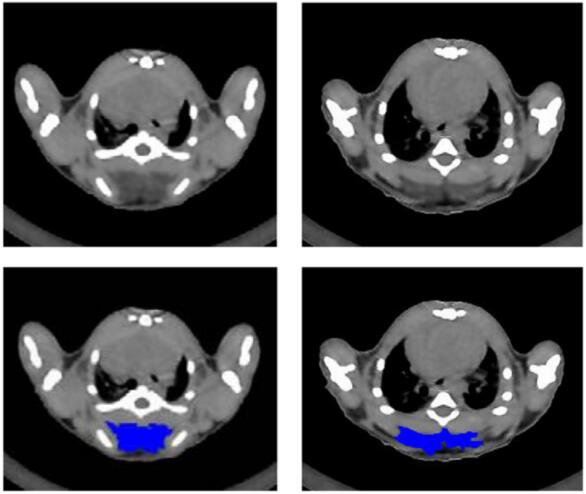

在實驗中,確定小鼠棕色脂肪組織數(shù)量的能力在肥胖和糖尿病的研究中至關(guān)重要。以下為使用Micro-CT對小鼠肩胛部位棕色脂肪的分離示意圖。

圖 4 小鼠肩胛部位橫截掃描圖。藍(lán)色代表棕色脂肪區(qū)域,左右為兩種不同形態(tài)的棕色脂肪。